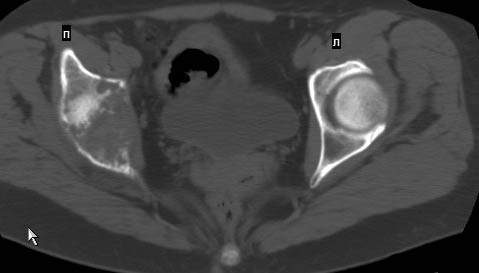

Сохранная по соматической патологии женщина ,47 лет. В 1996 г. установлен диагноз- cr левой молочной железы Т2N1Mo (2б)- проведено комплексное лечение- мастэктомия по Холстеду, ДГТ, 5 курсов ПХТ по схеме CMF. Сейчас менопауза уже 6-7 лет. В декабре 2004 года на профилактической остеосцинтиграфии с Тс99- выявлен единичный очаг повышенной фиксации препарата в зоне правой седалищной кости, рекомендована Рентгенография костей таза, выполнена- без патологии. УЗИ брюшной полости и Р-графия легких от конца апреля 2005 года - без патологии. Приблизительно 3 месяца назад появился болевой синдром в правом т/бедренном суставе с тенденцией к усилению. На рентгенограмме таза от мая 2005 года по заключению Рентгенолога очагов остеодеструкции не выявлено. Сегодня сделал ей Кт костей таза (картинки в приложении)- очаг деструкции в правой седалищной кости в зоне крыши вертлужной впадины. Что можно и нужно сделать? Жду советов, мнений, предложений по дальнейшей тактике ведения больной. С уважением, Корнев А.В.